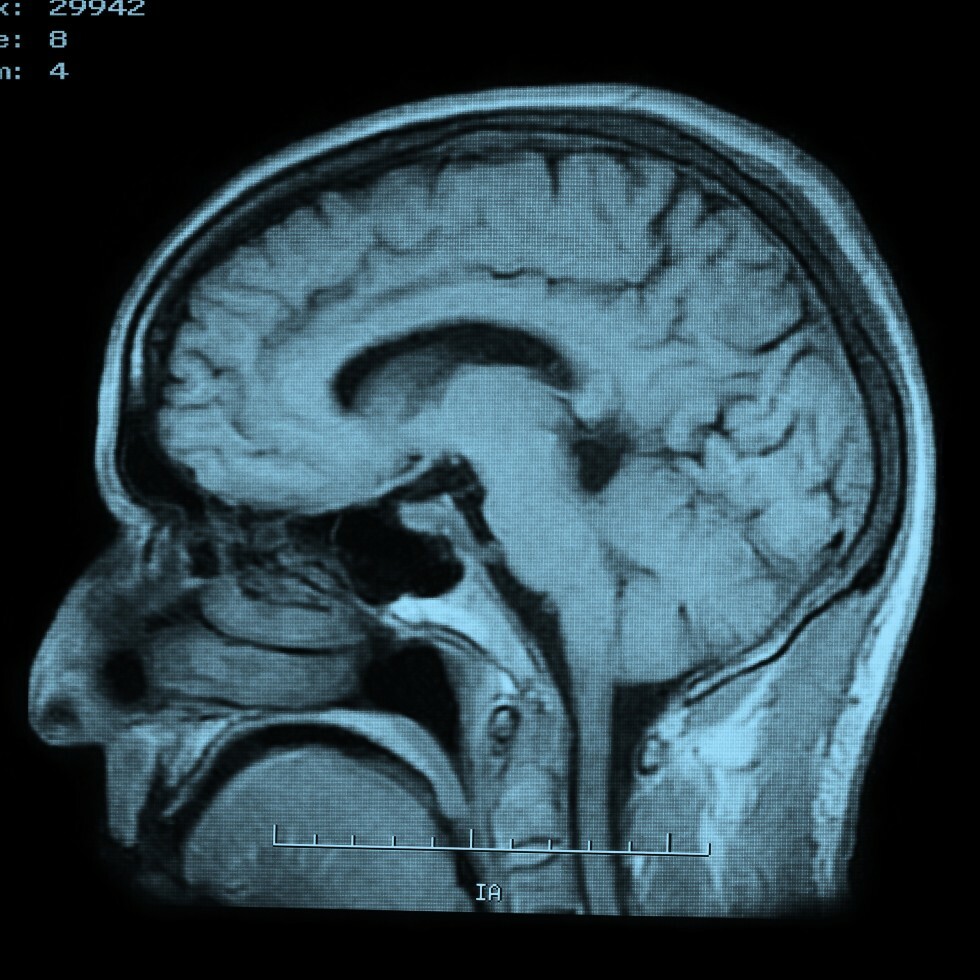

MRI - Brain

What is an MRI of the Brain?

MRI of Brain

MRI Brain

Magnetic resonance imaging, or MRI, is a method of producing detailed pictures of organs and body tissues by exposing a patient to radio waves in a strong magnetic field. The field is measured and analyzed by a computer, which forms two or three-dimensional images that may be viewed on a TV monitor. Because it uses radio waves and a magnetic field rather than x-rays, there is no exposure to radiation. An MRI of the brain provides high quality two and three-dimensional images that can show both surface and deep brain structures with high clarity and accurate anatomical detail. An MRI is used to detect changes that occur in these structures over time.

Why might my doctor recommend an MRI of the brain?

If you experience seizures, memory loss, hearing loss, or dizziness your doctor may recommend an MRI of the brain to detect, diagnose, and/or assess tumors, multiple sclerosis, stroke, dementia, hemorrhage, cerebral palsy, or meningitis in addition to other diseases of the brain. An MRI of the brain also is useful in post-operative evaluations.